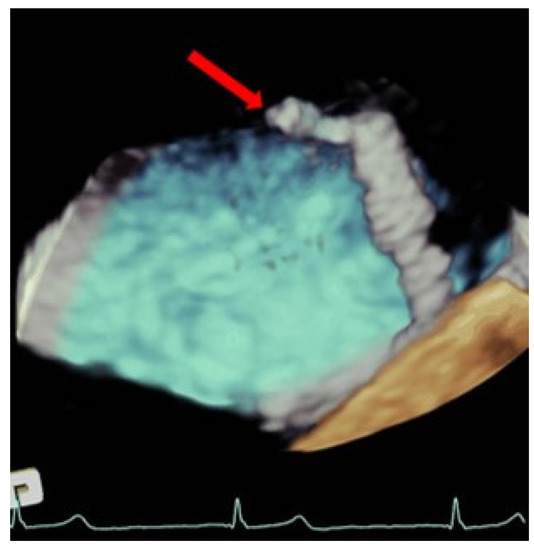

5. Post-TEER Persistent Atrial Septal Defects

Post-TEER persistent atrial septal defects (ASD) have a considerably high incidence, which ranges from 40 to 50% in the available studies [25,26]. Previous studies show inconsistent findings, with some reporting worse clinical outcomes and increased mortality in patients with significant defects [25], while others point to a low clinical impact in the long-term follow-up [26]. Further studies should be conducted to obtain conclusive information on this matter.

Interatrial septal dissection rarely occurs after mitral valve TEER. It consists of a false lumen formation between the mitral valve annular area and the atrial septum, and it might be necessary to treat it with a percutaneous closure device.

TEE allows for the assessment of the ASD, morphology, and size, it being superior to visualization through 3D-TEE. If the percutaneous closure of the ASD is necessary, the TEE is essential in guiding the procedure [27] (Figure 7).

Figure 7.

Persistent atrial septal defect. (Left) Three-dimensional transesophageal echocardiogram image showing a large atrial septal defect with tearing of the tissue through the transseptal puncture area (yellow arrow) from the left atrium. (Right): Two-dimensional transesophageal echocardiogram showing an Amplatzer device closing the iatrogenic atrial septal defect (red arrow).